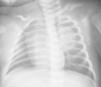

La paciente permanece asintomática, con ganancia ponderoestatural adecuada y desarrollo psicomotor normal. Al mes de vida, se realiza una radiografía de tórax (fig. 2) y RM para confirmación de la sospecha diagnóstica. Se solicita esofagograma que descarta comunicación con el quiste. A los 9 meses de edad, se realiza una quistectomía programada mediante videotoracoscopia. La anatomía patológica confirma el diagnóstico de formación quística, compatible con quiste broncogénico.